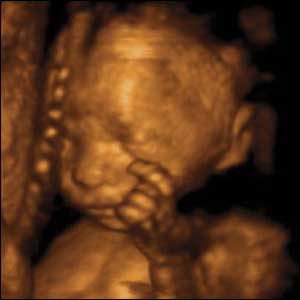

10 týdnů, 6 mm

V deseti týdech plod může plod různě pohybovat rukama a nohama.